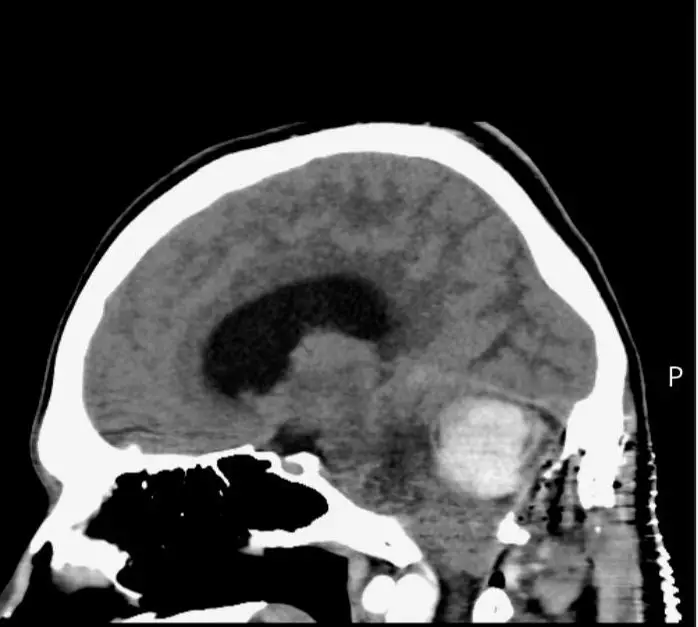

However, when his symptoms became even worse in the summer of 2025, Taylor demanded an MRI test, which tragically revealed that he had a haemangioblastoma brain tumour which was 'bigger than a golf ball'.

According to Macmillan Cancer Support, a haemangioblastoma is a rare, slow-growing tumour which is not cancerous. It can still be fatal and cause issues when the tumour presses on the surrounding brain.

It grows in a part of the brain known as the cerebellum, which coordinates balance, posture and motor learning. Sometimes it can also grow in the brain stem or spinal cord.